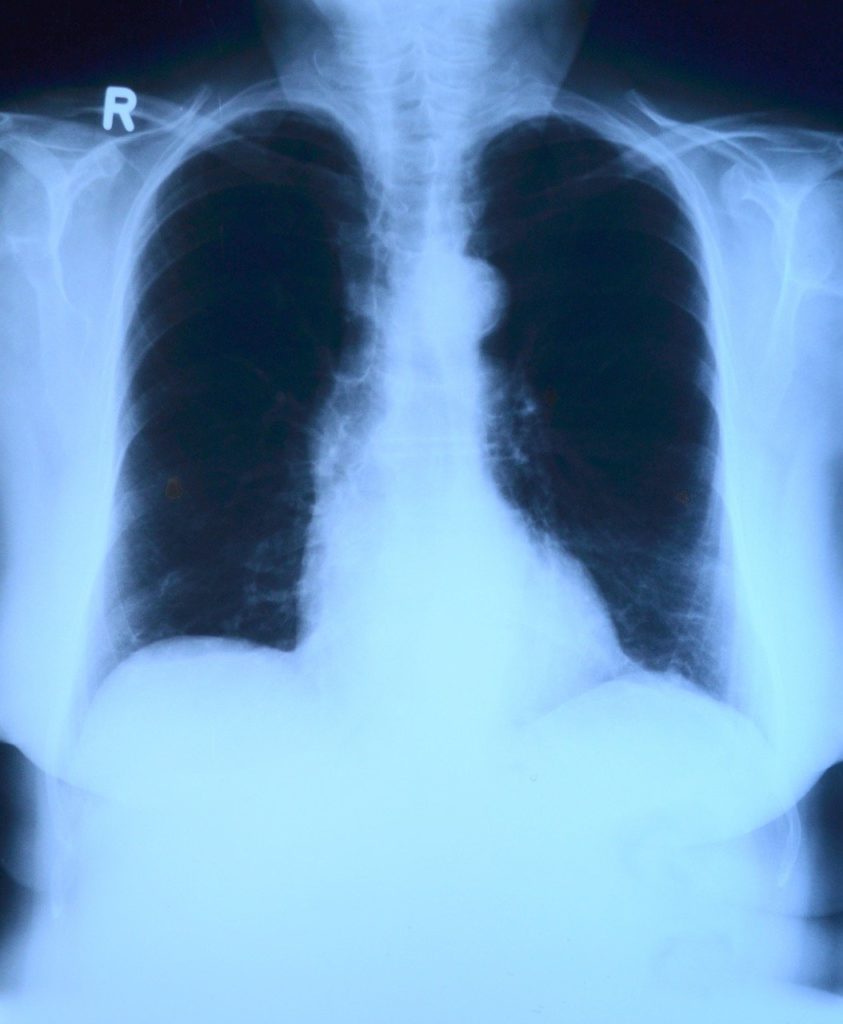

Рентген легких применяется для более тщательного исследования, если заподозрены конкретные заболевания. Этот вид обследования является более информативным, так как позволяет получить более четкий снимок.

- Рентген обладает большим качеством и информативностью изображений, так как рентгеновский снимок по размеру больше, чем флюорограмма.

- По флюорографии врач может оценить легочный рисунок и состояние тканей органа. В результате рентгена доктор получает снимок грудной клетки. При изучении снимка он обращает внимание на структуру мягких тканей и костей.